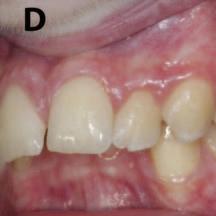

After lunch, orthodontist Dr Shane Higgins spoke on orthodontic problems and solutions in managing the mixed dentition. Using a range of clinical examples, he outlined the treatment planning and decision-making process around proposed extractions of first permanent molars of poor prognosis, impacted incisors, and double teeth. He gave tips on how to measure crowding, and discussed the importance of a timely orthodontic consultation to plan for future treatment. He concluded by saying that issues in the mixed dentition can be complex, and timing is crucial, but there are guidelines available to assist clinicians, and he advised seeking specialist advice if you’re not sure how to proceed.